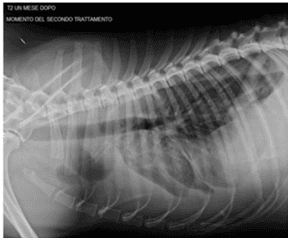

Effects of Autologous Microfragmented Adipose Tissue on Bone Healing: A Blinded, Prospective, Randomised Canine Clinical Trial

Luca Pennasilico, Caterina Di Bella, Sara Sassaroli, Alberto Salvaggio, Francesco Roggiolani, Angela Palumbo Piccionello, MDPI, 2023